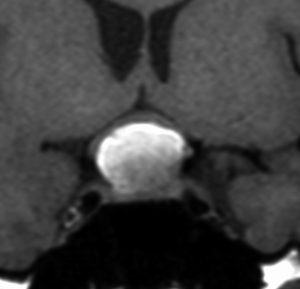

多少取り残しても再発しない

29歳の女性が高プロラクチン血症による月経不順で発症しました。視野検査では両耳側半盲が認められました。

手術所見では,多量のコレステリン結晶が流出しました。腫瘍実質は硬く正常下垂体との剥離はできませんでした。黄色肉芽種の可能性もあるので,あ全摘出にとどめて手術を終了しました。T2強調画像で黒い低信号の縁取りがあり内部に不均一なのう胞内容液が見えるのが特徴とも言えます。

3年後の画像です。腫瘍の再燃増大はありませあん。視野は正常化して,下垂体機能も正常化しホルモン補充はありません。